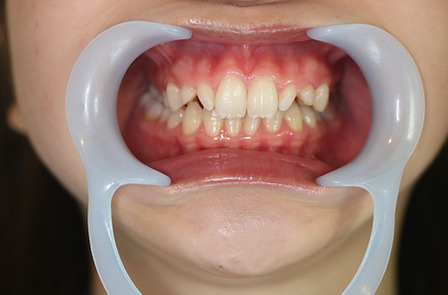

1矯正・マウスピース【治療例1】

治療前

治療後